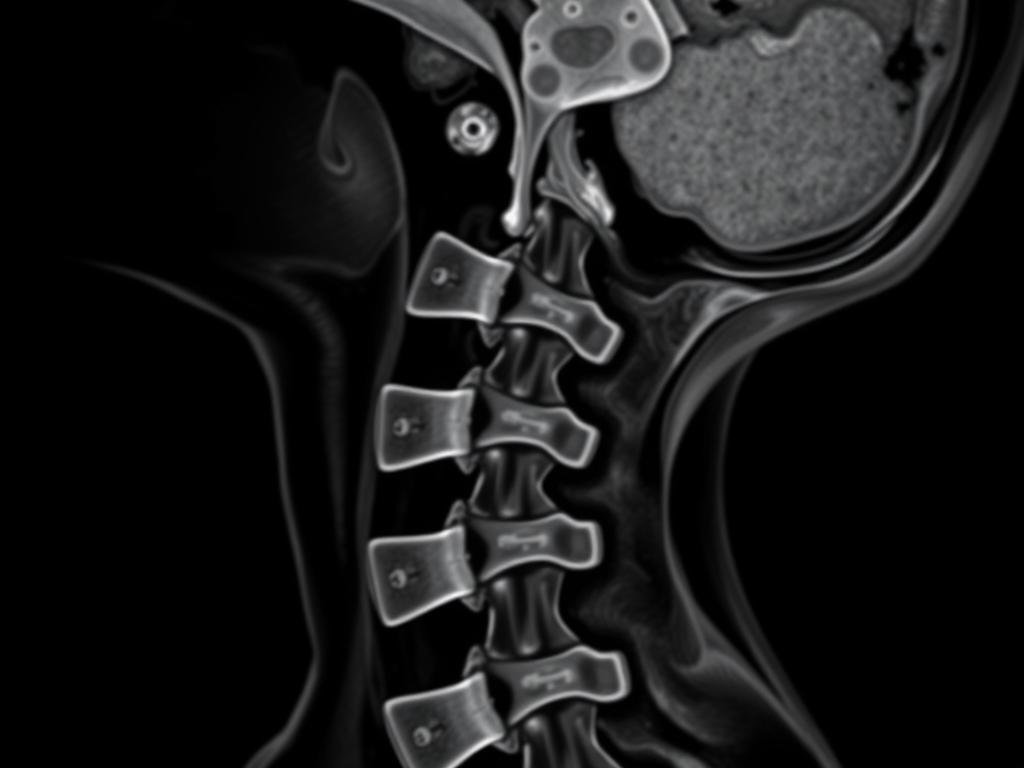

MRT-Aufnahme der Halswirbelsäule

Zur Absicherung der Diagnose und zum Ausschluss schwerwiegender Erkrankungen können verschiedene bildgebende Verfahren eingesetzt werden:

- Röntgen: Zeigt knöcherne Strukturen und kann Verschleißerscheinungen oder Fehlstellungen sichtbar machen

- Magnetresonanztomographie (MRT): Stellt Weichteile wie Bandscheiben, Nerven und Muskeln detailliert dar

- Computertomographie (CT): Liefert präzise Bilder der knöchernen Strukturen